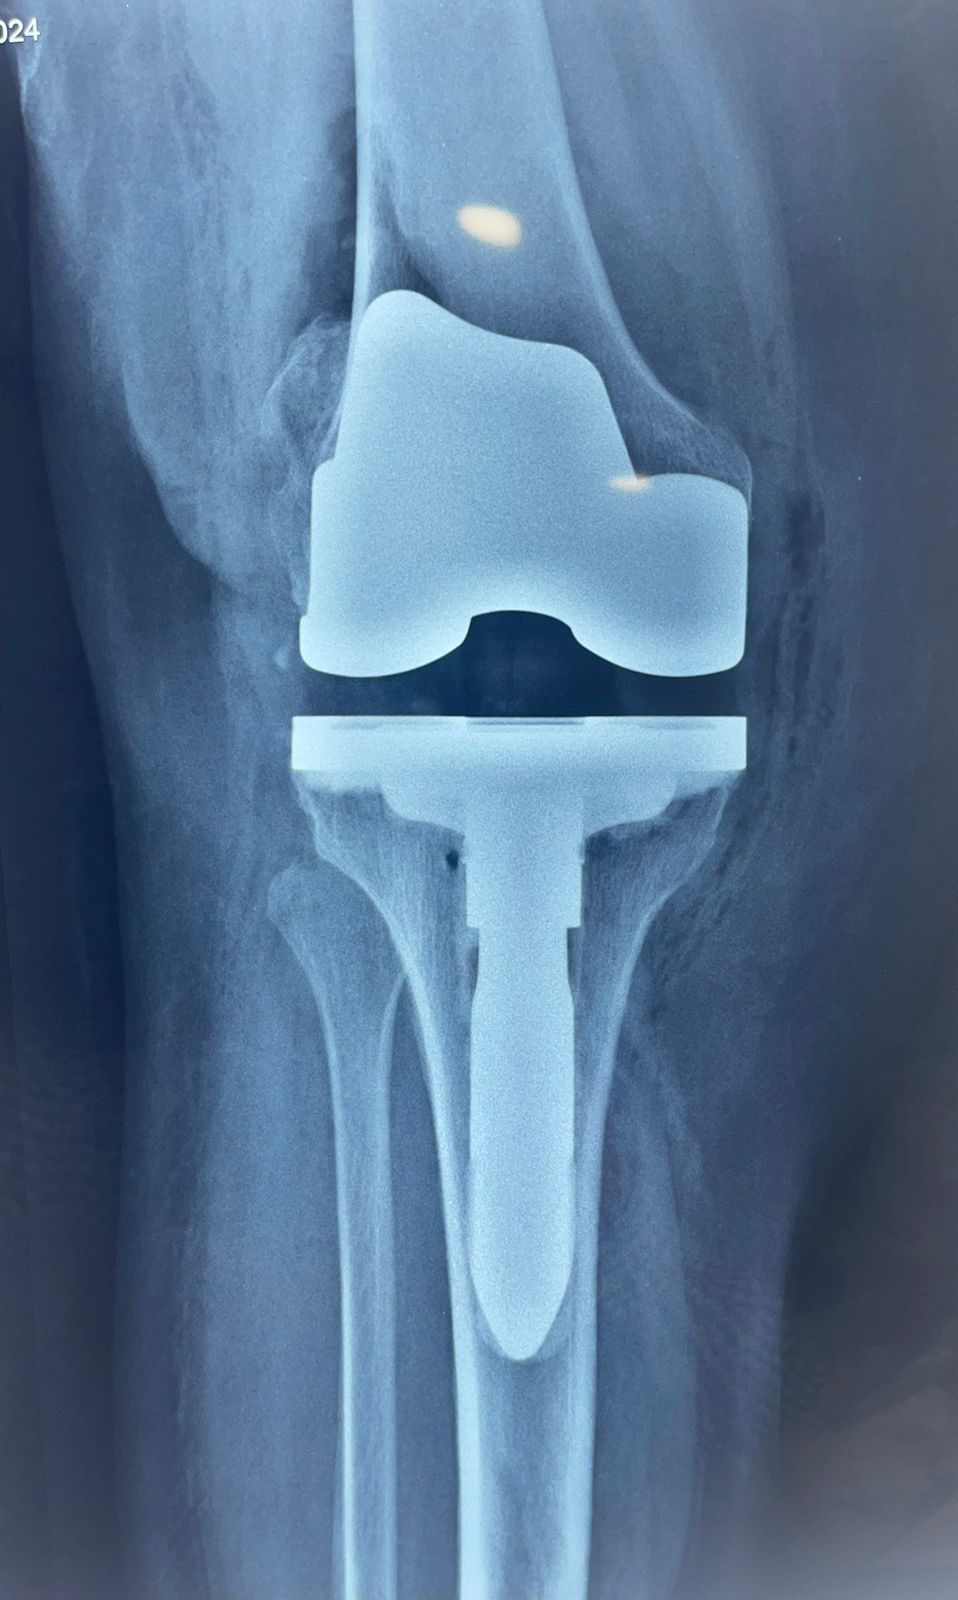

Fotos y videos